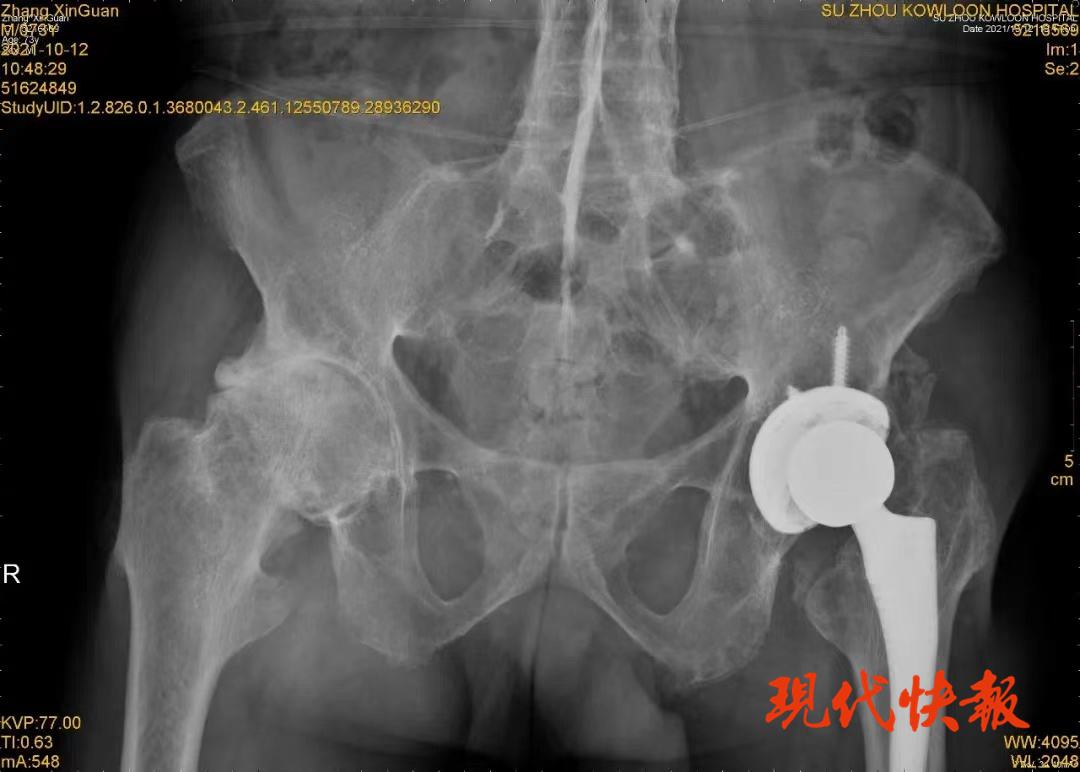

七旬老伯置换髋关节,术后第二天下地行走

现代快报讯(通讯员 沈贤)近日,73岁的张老伯因右侧髋关节疼痛明显,无法长时间站立行走,来到苏州九龙医院就诊。骨科主任医师刘进炼、刘春风及团队,为其成功进行了右侧髋关节置换手术。术后的第二天,张老伯便可以下床活动了。

十年前,他的两侧髋关节出现疼痛的情况,左侧尤其明显,疼痛反复发作并且逐步加重,于是在苏州九龙医院接受了左侧髋关节置换术。骨科团队热情周到的服务和无微不至的照顾给张老伯一家留下了良好的印象。

十年后,张老伯的右侧髋关节疼痛发作,并且越来越频繁。因为难以忍受的疼痛被限制在家里,被限制在床上。思虑许久,他决定再次来到苏州九龙医院,进行右侧髋关节置换手术。

张老伯当年自费三万余元更换左侧髋关节。十年来,随着人工髋关节被纳入政府医用耗材集中采购行列,髋关节置换手术费用明显下降,张老伯选择了质量更好的进口关节,自费仅一万元,关节材料的使用寿命有90%的机会超过15年。

由于疼痛感不强烈,此次手术结束当天,张老伯就能够在病床上自由地屈伸,第二天查房时,张老伯没想到在医护人员搀扶指导下,竟能下地行走,他激动地说:“本来想着不管花多少钱都要治疗,因为人一旦瘫在床上就废了。这次手术不仅费用没花多少,还能这么快下床活动,真的是奇迹啊。”